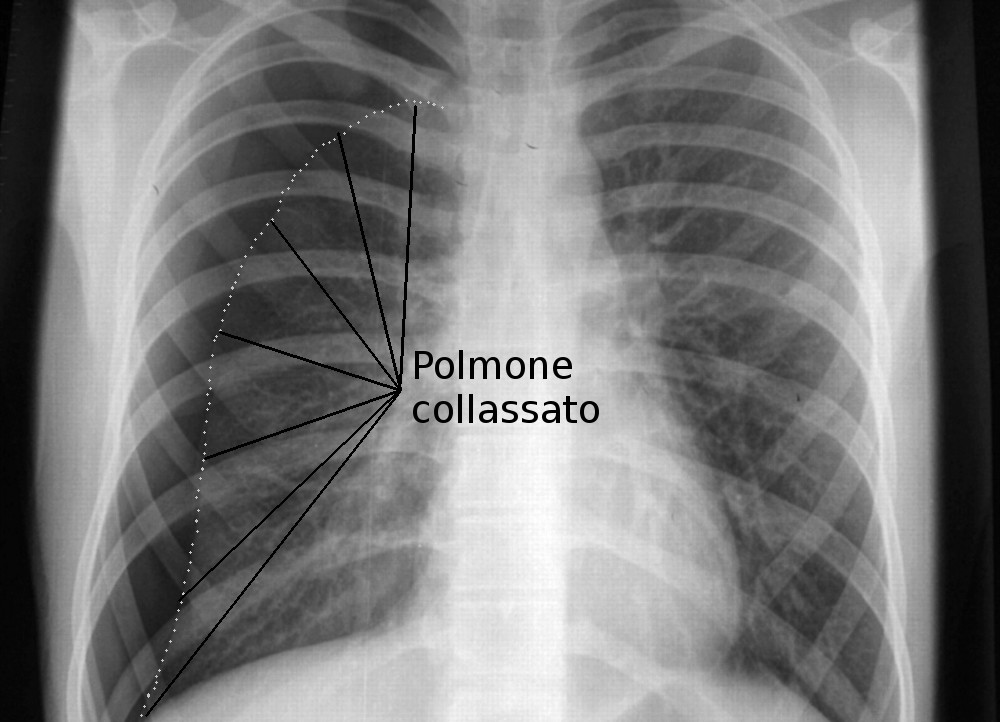

Pneumotorace

- Descrizione: Presenza di aria nello spazio tra le Pleure.